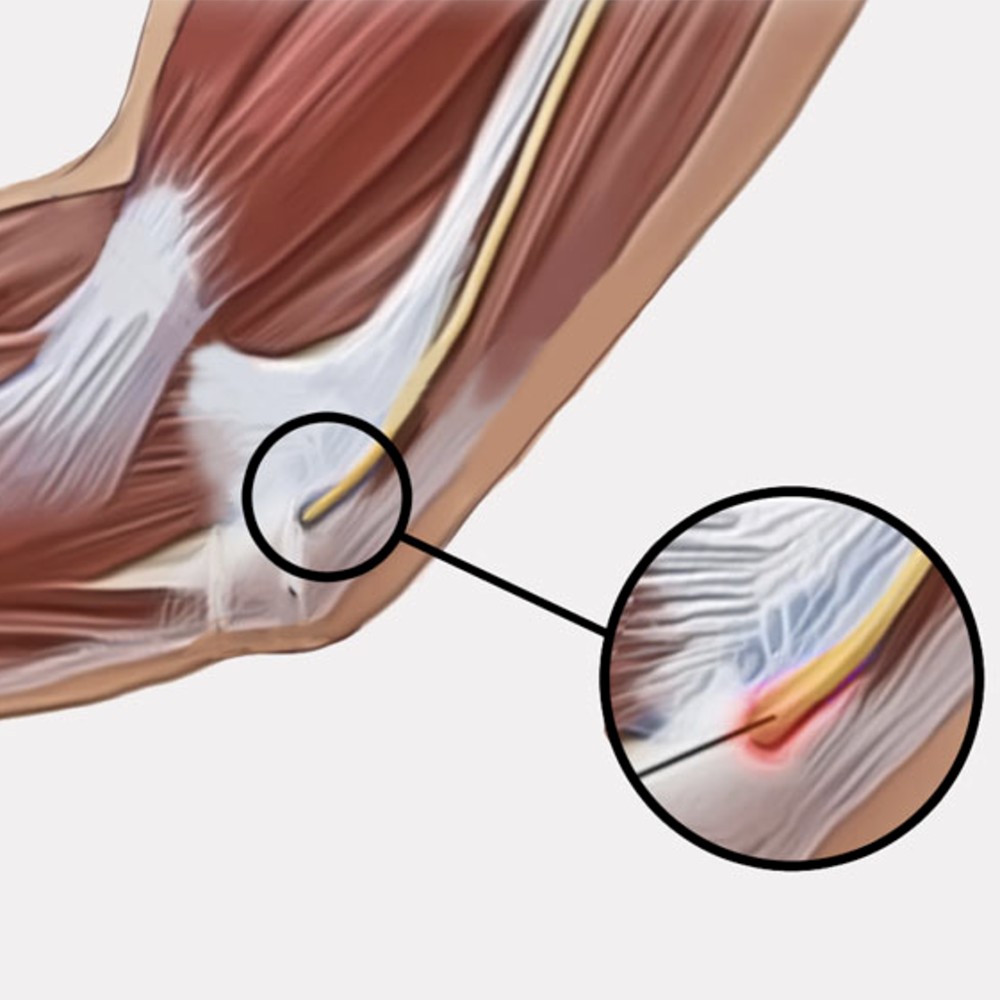

Κατασκευή από ύφασμα τριών στρωμάτων: Εξωτερική επένδυση από αυτοκόλλητο polyamide και εσωτερικά από foam «Unipren» και «Jersey». Ειδικά σχεδιασμένος για τη βελτίωση της ωλένιας νευρίτιδας συγκρατώντας ταυτόχρονα την άρθωση του αγκώνος στην επιθυμητή θέση έκτασης. Φέρει διαμορφώσιμες λάμες αλουμινίου για τον περιορισμό της κάμψης ώστε να ελαχιστοποιείται ο πόνος. Ο νάρθηκας είναι ελαφρύς, δύναται να χρησιμοποιηθεί και κατά την διάρκεια της νύχτας, αποτρέποντας την ακούσια κάμψη του αγκώνος. Στην περιοχή της κοιλότητας του αγκώνος ο νάρθηκας είναι ανοιχτός, για λόγους υγιεινής φροντίδας, και αλλαγής των επιδέσμων χωρίς να αφαιρείται (αν έχει προηγηθεί χειρουργείο). Αμφιδέξιος.

- Ωλένια νευρίτιδα

Κατασκευή από ύφασμα τριών στρωμάτων: Εξωτερική επένδυση από αυτοκόλλητο polyamide και εσωτερικά από foam «Unipren» και «Jersey». Ειδικά σχεδιασμένος για τη βελτίωση της ωλένιας νευρίτιδας συγκρατώντας ταυτόχρονα την άρθωση του αγκώνος στην επιθυμητή θέση έκτασης. Φέρει διαμορφώσιμες λάμες αλουμινίου για τον περιορισμό της κάμψης ώστε να ελαχιστοποιείται ο πόνος. Ο νάρθηκας είναι ελαφρύς, δύναται να χρησιμοποιηθεί και κατά την διάρκεια της νύχτας, αποτρέποντας την ακούσια κάμψη του αγκώνος. Στην περιοχή της κοιλότητας του αγκώνος ο νάρθηκας είναι ανοιχτός, για λόγους υγιεινής φροντίδας, και αλλαγής των επιδέσμων χωρίς να αφαιρείται (αν έχει προηγηθεί χειρουργείο). Αμφιδέξιος.